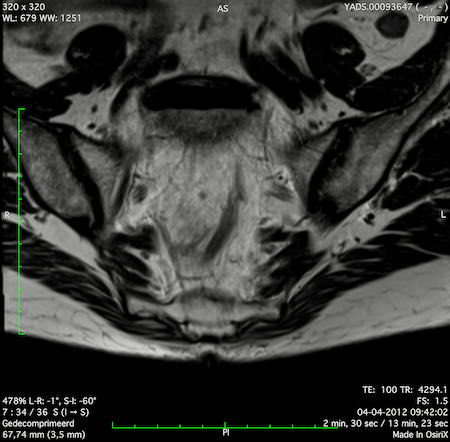

Hình ảnh

Các hình ảnh được cung cấp cho thấy ung thư biểu mô tế bào nhẫn với tình trạng dày lan tỏa thành trực tràng, hình ảnh bia bắn điển hình, và sự xâm lấn mỡ mạc treo trực tràng.